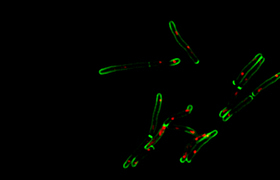

Working with supervisor, Professor Warner, the researchers performed non-invasive collection of bioaerosol, or exhaled breath, of TB patients in a respiratory aerosol sampling chamber (RASC). They then used fluorescent microscopy, together with a mycobacteria-specific viability probe, to detect and identify live M. tb in the collected samples.

“When a fluorescent probe, specific to live mycobacteria, was developed by collaborators Dr Mireille Kamariza and Professor Carolyn Bertozzi at Stanford University, it opened up the possibility to use sensitive microscopy to find these very small numbers of bacteria in liquid samples.”